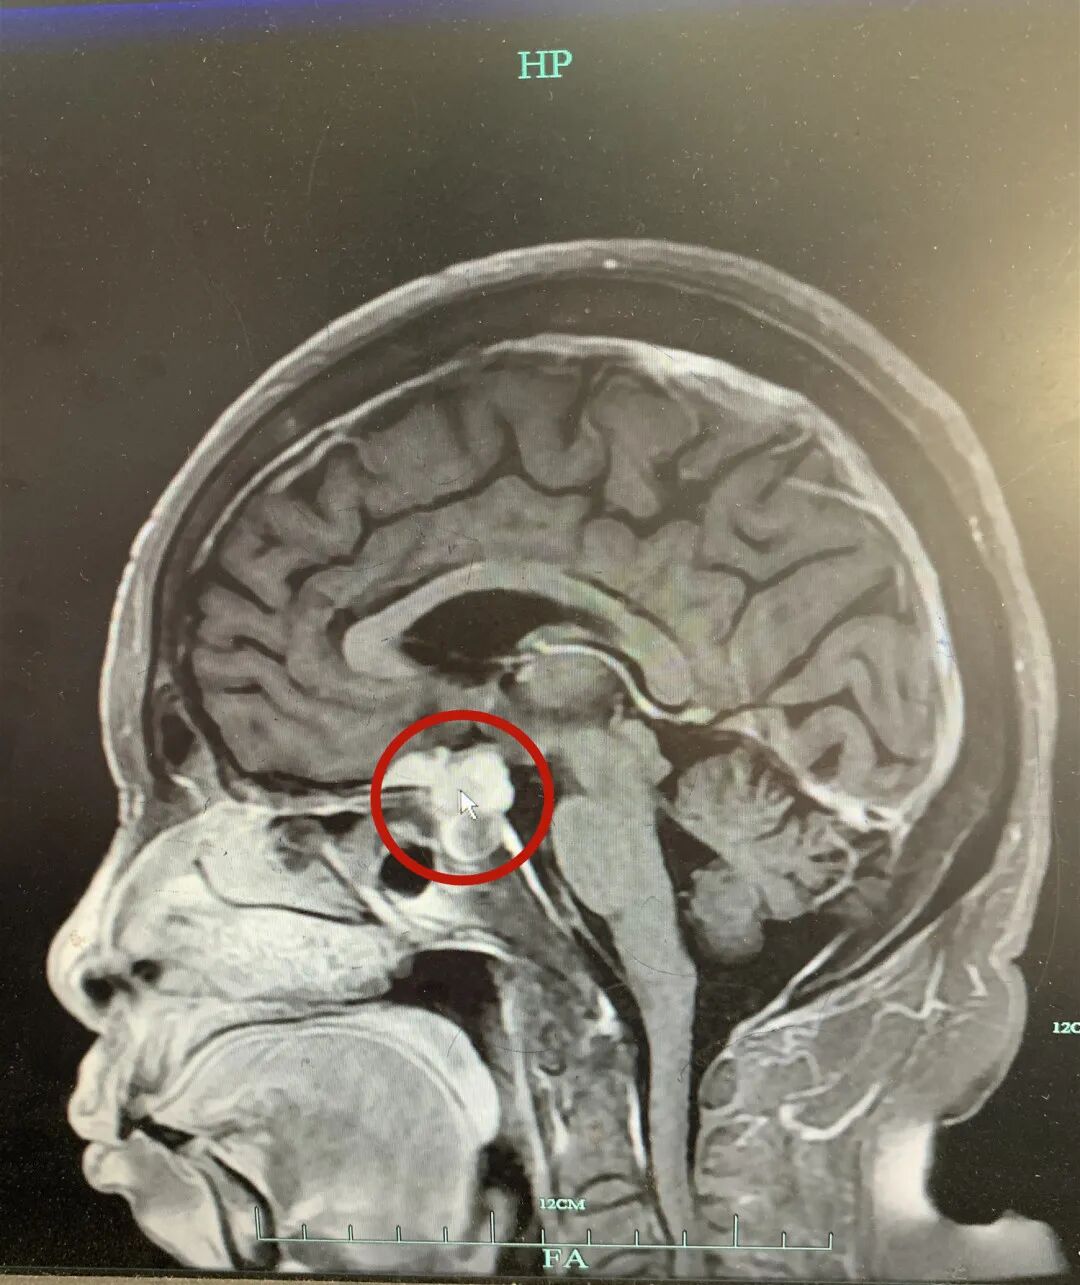

根据影像数据显示,鞍区的肿块大小约21*15*20mm,已经压迫到了视神经

精准手术助其渡难关——浙一神外之江病区完成高难度蝶鞍区肿瘤切除术